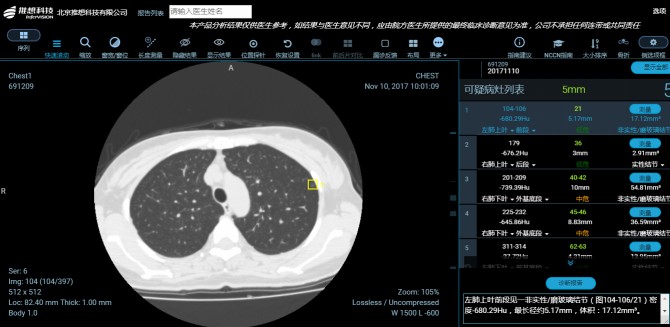

据悉,推想科技智能CT辅助筛查产品在早期肺癌筛查应用中,以其高性能的并行运算能力,有效挖掘肺癌的核心特征点,高效判断不同序列影像是否存在疑似癌症的特征,实现肺癌早诊、早治的技术性突破。通过与医生的对比,推想科技智能CT辅助筛查产品不仅能够大大提升肺癌筛查的效率,同时人工智能对半实性与磨玻璃结节等早期肺癌征兆展现出了优越的敏感性,能够帮助放射科医生提升诊断的准确率,降低漏诊率。

红河州第三人民医院、红河州肿瘤医院作为国家级肺癌低剂量CT筛查项目点,依托世界顶级的Aquilion ViSION 640层微量子电影高端CT,放射科诊断医师在早期肺癌筛查方面已经具备了丰富的诊断经验,而今,推想AI-CT在该院成功上线试运行,使医院放射影像科如虎添翼,让影像诊断医师拥有了“第二双眼睛”。医院将使用 “AI辅助,人工诊断”这一筛查方式,更加准确地判断、分析病灶。积极借助AI技术的应用,助力红河州第三人民医院、红河州肿瘤医院实现精准影像诊断之路,更好地服务于红河州乃至更广泛地区的民众,让就诊者能获取更加精准的诊疗报告。